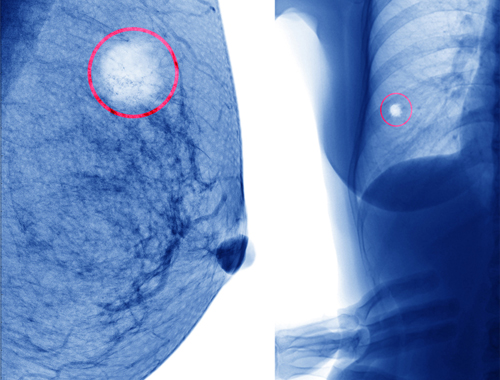

Eine Brustzyste ist eine Ansammlung von Flüssigkeit in der Brust. Normalerweise ist es eine kleine mit Flüssigkeit gefüllte Blase, die ungefähr die Größe einer Haselnuß hat, aber auch kleiner sein kann. Es gibt keinen besonderen Grund für die Entstehung von Zysten.

Diese Art von Zysten sind am häufigsten, es gibt jedoch auch Zysten mit fester Form.

Es existiert auch eine andere Art von Brustzysten, die sogenannten Fibroadenome. Diese verlaufen meist schmerzfrei und ohne Symptome und sind feste, bewegliche, ungleiche und unebene Knoten, die sich beim Abtasten zwischen den Fingern wie eine Haselnuss leicht bewegen. Fibroadenome sind ebenfalls gutartig.